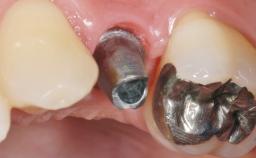

Early Placement of an Implant in a Maxillary Right Central Incisor Site

This 41-year-old female patient was referred to the clinic for the replacement of the right central incisor, since the tooth had developed a root fracture in the long axis that made extraction necessary. The healthy, non-smoking patient was first seen with the tooth still in place. A detailed Esthetic Risk Assessment was performed.The patient was worried about her dental esthetics and had high expectations for a successful treatment outcome from an esthetic point of view. The patient had a medium lip line that displayed parts of the gingiva in the anterior maxilla upon smile.

Abutment Type Customized

Placement Protocol Early or late implant placement

Bone Volume Deficient horizontally, allowing simultaneous augumentation